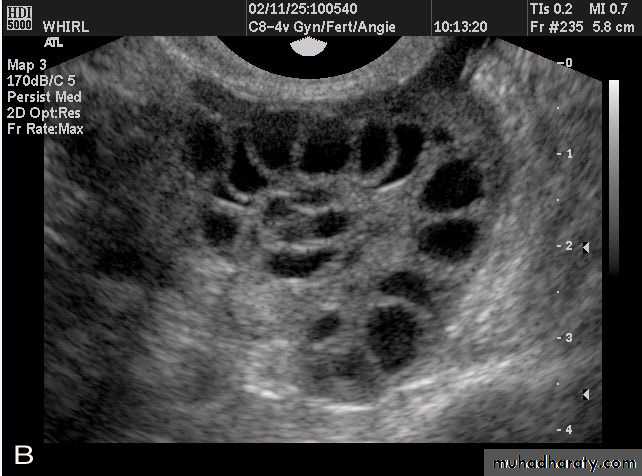

POLYCYSTIC OVARY SYNDROME

Images from women with differing expressions of the four major subtypes of the metabolic syndrome associated with polycystic ovary syndrome (A–D). The images exhibit quite differing ultrasonographic appearances in the size and distribution of follicles within PCOS ovaries. A recent corpus luteum is clearly visible in the ovary in panel (D).

• POLYCYSTIC OVARY SYNDROME

Images from women with differing expressions of the four major subtypes of the metabolic syndrome associated with polycystic ovary syndrome (A–D). The images exhibit quite differing ultrasonographic appearances in the size and distribution of follicles within PCOS ovaries. A recent corpus luteum is clearly visible in the ovary in panel (D).• POLYCYSTIC OVARY SYNDROME

Images from women with differing expressions of the four major subtypes of the metabolic syndrome associated with polycystic ovary syndrome (A–D). The images exhibit quite differing ultrasonographic appearances in the size and distribution of follicles within PCOS ovaries. A recent corpus luteum is clearly visible in the ovary in panel (D).The Oviduct (Fallopian Tube)